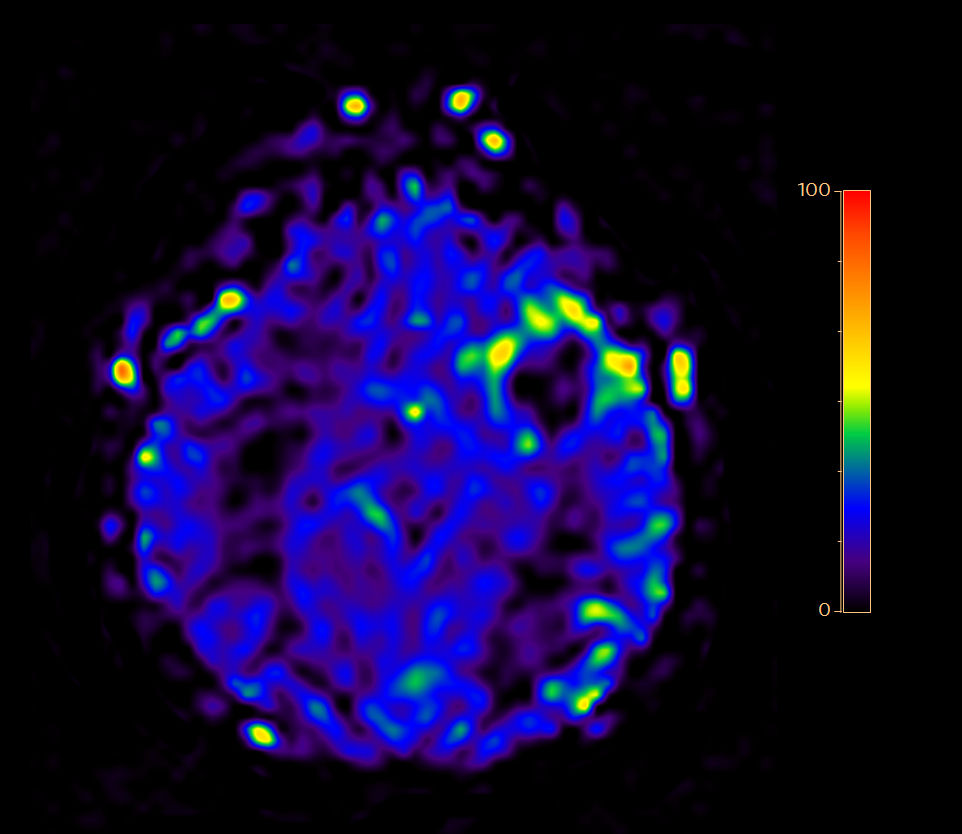

Axial T2* Perfusion (60 dynamics)

-